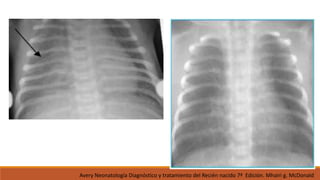

• Rx de Tórax

IMÁGEN

PRUEBAS DIAGNÓSTICAS: • Hemograma •PCR • Urocultivo (RN >7 días) Evaluación de sepsis • Cultivos de lcr. • Hemocultivo MICROBIOLÓGICAS • Rx de Tórax • Ultrasonido pulmonar IMÁGEN Neumonías neonatales Acta Pediatr Esp. 66(10) 481-486